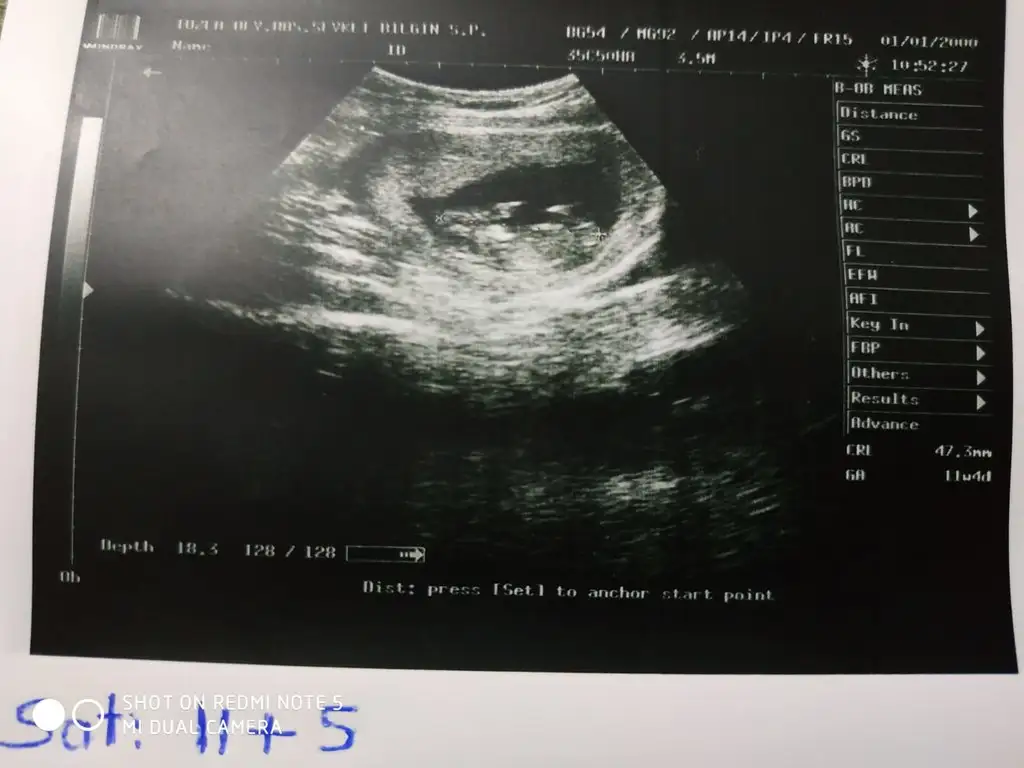

Merhaba,bu usg de cok gel git yaşadım açıkçası

Merhaba,bu usg de cok gel git yaşadım açıkçasıkafa yapısı erkek gibi nubu kız gibi.ama oyumu kızdan yana kullanıyorum :))

Bu konuda tecrubeli misiniz ?Merhaba,bu usg de cok gel git yaşadım açıkçasıkafa yapısı erkek gibi nubu kız gibi.ama oyumu kızdan yana kullanıyorum :))

Canım bugün tahmin yapmıştın doktora gittim erkeğe benziyor dediMerhaba,bu usg de cok gel git yaşadım açıkçasıkafa yapısı erkek gibi nubu kız gibi.ama oyumu kızdan yana kullanıyorum :))

Sağdaysa kız Canım ama cok tutmayan var bu teoride 11 12 . Ci haftaları bekle derimYüzde olarak dersen ne dersin kesedeki hali de sağdaydı karından usgde

11+3, yorumların tutma oranı ne acaba ben iyice meraklandımKac haftalik ben kiz diyorum

Erkek diyorum

Bi tek ben. Mi erkek dedimErkek diyorum

Ben kafa yapısı ve duruşa göre dedim nub tan anlayanları dikkate al derimAy evetemin misin nub falan baktın mı güzelce